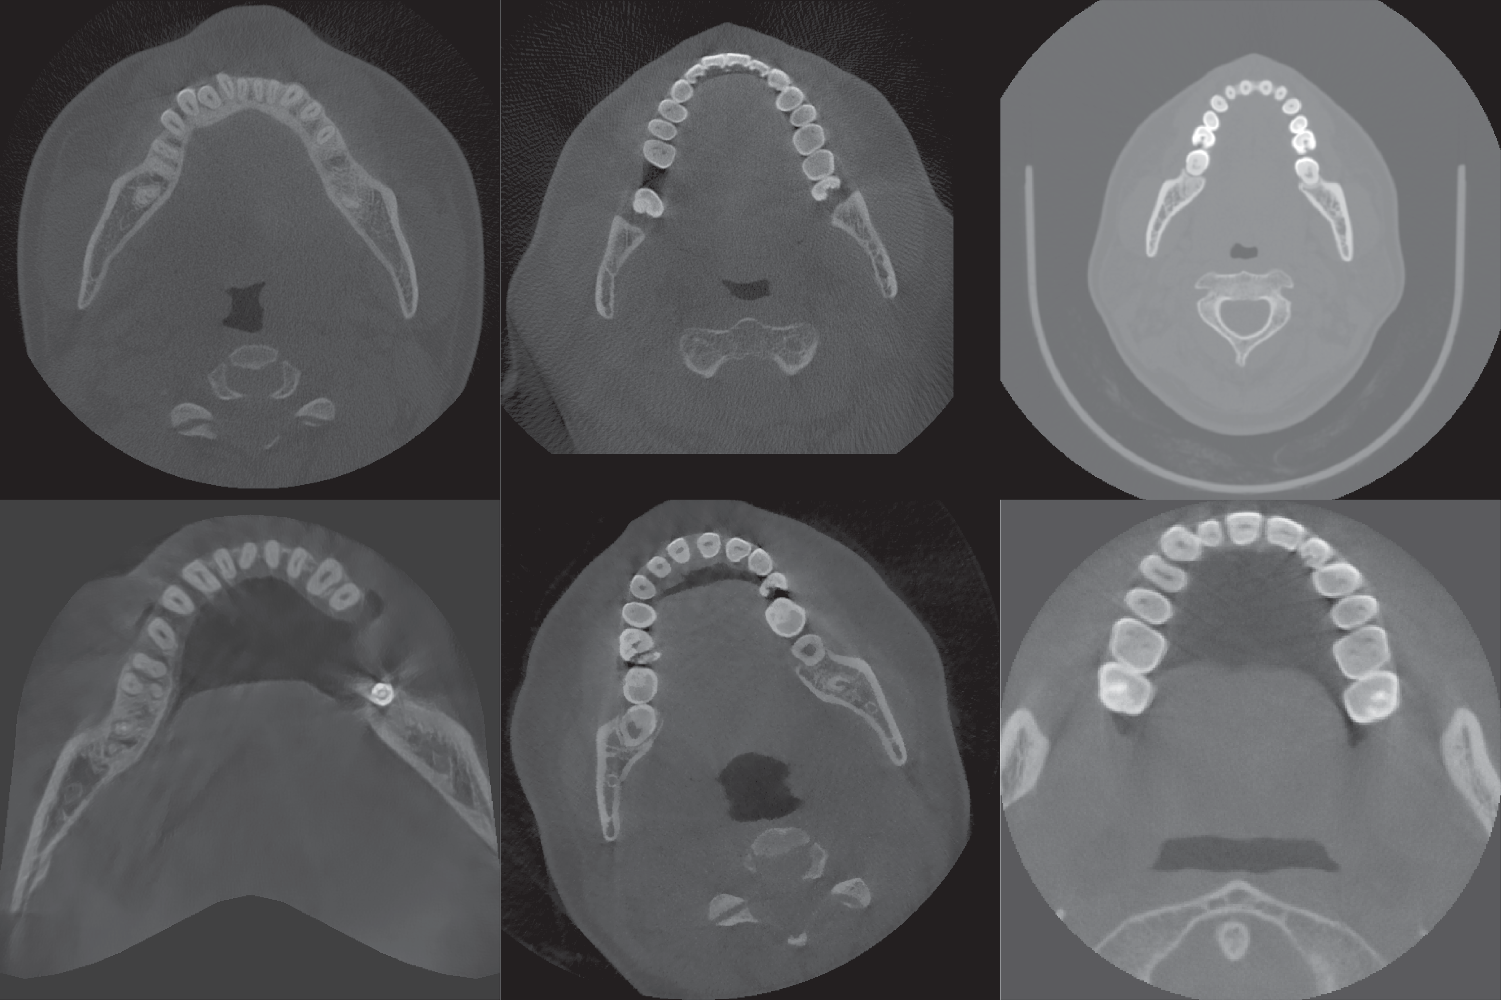

Fig. 2 | International Journal of Oral Science